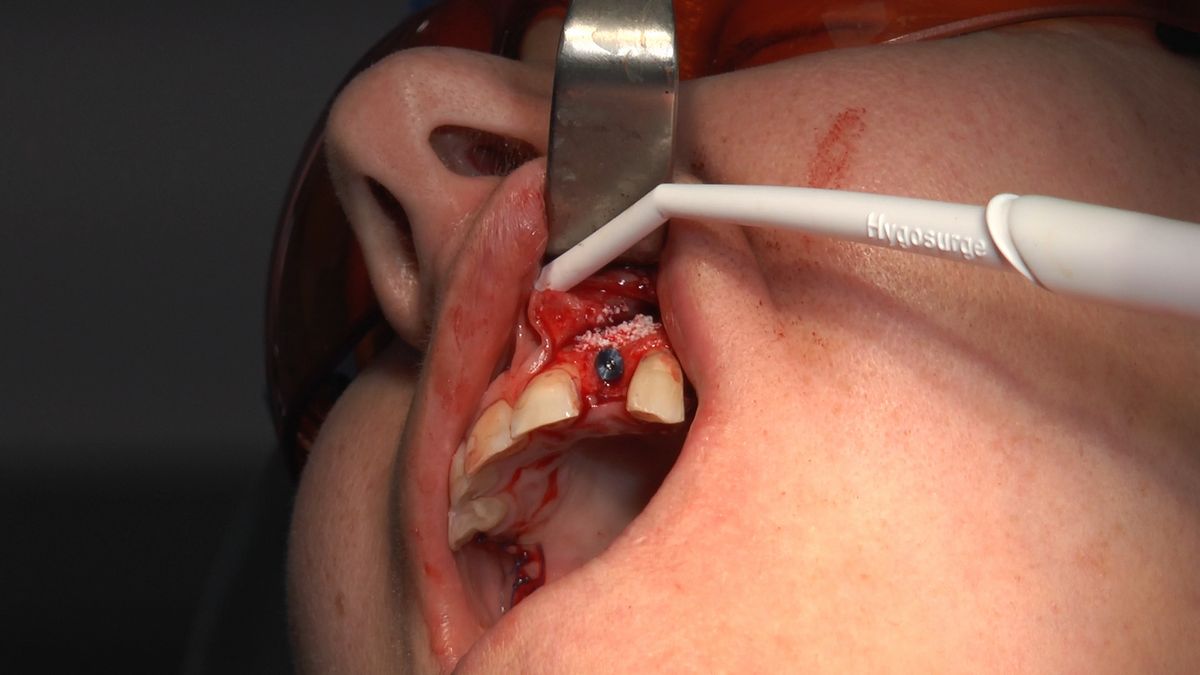

W ostatni weekend czerwca 2018 roku kursanci II Sezonu Preludium Implantologii odbyli piątą, finałową sesję, która w całości podporządkowana była praktyce. W ciągu dwóch dni zabiegowych Lekarze uczestniczący w szkoleniu przeprowadzili szereg zabiegów pod kierunkiem dr n.med. Violetty Szycik. Wszczepili 17 implantów oraz przeprowadzili ekstrakcje i zabiegi regeneracyjne kości. Zabiegi były wykonywane także w sedacji dożylnej z udziałem specjalisty anestezjologii i intensywnej terapii dr Jolanty Grzybowskiej. Preludium implantologii to nowy program edukacyjny dla adeptów implantologii stomatologicznej, którego celem jest wprowadzenie do implantologii poprzez pozyskanie wiedzy w szerokim zakresie i uwzględnieniem szczegółów mających decydujące znaczenie dla powodzenia leczenia implantologicznego. Ale tak jak wszystkie szkolenia w Instytucie Vivadental, w tym wiodące Practiculum Implantologii, zorientowane jest na praktyce i samodzielnym wykonywaniu zabiegów pod kierunkiem Mentora. To najlepsza edukacja w medycynie zabiegowej, a zarazem najlepszy start do implantologii.